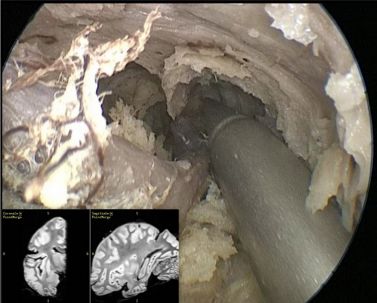

使用两把改良后不同长度和角度的“S”形吸引器,可以实现后岛叶完全切除,到达岛沟上部,即岛后点水平部(图7)。

图7. 神经导航指向岛后点的内镜下观察。

变换内镜角度,切除前岛叶(图8)。内镜头背对颞中回表面,朝向额叶岛盖。依次分离短回和岛后回,识别岛盖纤维束,作为分离边界的标志。“S”形吸引器对前岛叶的分离很有帮助,可以达到岛前点。

图8. 前岛叶切除手术定位。为获得足够的岛叶短回视野,内镜镜头朝向额叶岛盖。